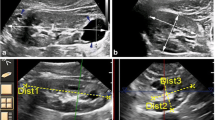

The software algorithm was designed to work with the manual designation of a long axis of a kidney (Fig. 1a). For the designation of the long axis, we rotated the vertical cross-sectional direction of CT images to identify the long axial cross-section. If we could not accurately extract all of the renal regions by the manual designation of the long axis, it was possible to draw a line of the long diameter of the kidney again as many times as needed, and the KV could be automatically measured again each time. In some cases, we repeated this procedure several times (the average number of times: 1.2, maximum number of times: 5). Given the long axis, the algorithm first estimates likelihood values of the kidney for every Hounsfield unit (HU) value from the voxels around the major axis. Next, the algorithm fit an ellipsoidal model to the images, allowing deformation caused by the cysts. Finally, the kidney regions are segmented by maximizing evaluation measures consisting of the sum of the likelihood values, edge strength on the boundaries, and fitness to the ellipsoidal model. Ultimately, this software provided the measurement of KV. Each measurement by this software took almost 10 s. Non-kidney structures (e.g. liver and spleen) were automatically identified and excluded from the measurement area.

a The algorithm was designed to work with the manual designation of a long axis of a kidney including cysts (yellow line). The automated extraction of the renal contour was implemented immediately after the manual designation of the long axis (green range). After the visual confirmation of the exact extraction region, the Vincent software can perform volumetric measure semi-automatically with just one click. b The relationship between Vincent TKV and accurate TKV at the time of development of the novel Vincent software. Vincent TKV was significantly correlated with accurate TKV (r = 0.9989). Circles identify single-patient data. c The relationship between ellipsoid TKV and accurate TKV at the time of the development of the novel Vincent software. Although we could see the correlation between ellipsoid TKV and accurate TKV, the confidence correlation factor (r = 0.9549) was lower than Vincent TKV. Circles identify single-patient data. d The relationship between 5 mm Vincent TKV and accurate TKV at the time of the development of the novel Vincent software. The correlation coefficient between 5 mm Vincent TKV and accurate TKV (r = 0.9963) was almost equal with Vincent TKV, and was higher than ellipsoid TKV. Circles identify single-patient data (color figure online)

With the use of these CT imaging data, we created a novel semi-automated kidney volumetric Vincent software. The median Vincent KV was 615.1 ml (IQR 446.0–952.7). There was no significant difference between rt. (median 564.9 ml, IQR 439.1–882.9) and lt. (median 653.2 ml, IQR 453.2–995.7) Vincent KV (p = 0.5451). The median Vincent TKV was 1254.2 ml (IQR 943.4–1874.5). Vincent TKV was well correlated with accurate TKV (correlation coefficient: r = 0.9989, Fig. 1b).

The median volume of ellipsoid KV was 697.1 ml (IQR 484.0–984.2). There was no significant difference between lt. (median 717.9 ml, IQR 526.4–977.4) and rt. (median 686.1 ml, IQR 480.0–982.6) ellipsoid KV (p = 0.6704). The median ellipsoid TKV was 1207.7 ml (IQR 955.9–1963.6). The correlation coefficient between accurate TKV and ellipsoid TKV was 0.9549 (Fig. 1c) and was lower than Vincent TKV.

For development novel software, we used CT scan with short slice thickness (median 0.63 ml) of the kidney. Therefore, to evaluate the usefulness of CT scan with long slice thickness for this novel software, the CT pictures were reorganized into 5 mm slice thickness (5 mm Vincent KV) and we evaluated the correlation between accurate TKV and 5 mm Vincent TKV. The median volume of 5 mm Vincent KV was 607.2 ml (IQR 441.2–937.4). There was no significant difference between rt. (median 554.3 ml, IQR 445.4–873.8) and lt. (median 657.1 ml, IQR 441.8–984.7) 5 mm Vincent KV (p = 0.6320). The median 5 mm Vincent TKV was 1272.5 ml (IQR 922.9–1883.0). The correlation coefficient between 5 mm Vincent TKV and accurate TKV (r = 0.9963, Fig. 1d) was almost equal with Vincent TKV and was higher than ellipsoid TKV.

Of course, this study has several limitations. Patient population used for analysis in our research has few patients. To improve the understanding of disease prognosis and clinical decision of the ADPKD phenotype, research should be conducted to evaluate automated systems in larger and more diverse patient populations. In particular, Fig. 3d showed that correlation was not accurate in a range of smaller KV volume in this study. Incidentally, there were several cases where it was difficult to identify renal cysts and surrounding organs including such as liver cysts and intestine automatically in cases with small renal volume. Although we consider it a coincidence result, we have to further increase the number of cases and study this method. In this study, some cases needed multiple measurements with the Vincent method. Other atlas-based or automated methods also failed due to the greatly different shape and size of the polycystic kidneys, and due to similar intensity in adjacent tissues. Likewise, from this, there are some real problems to measure accurate KV using the Vincent method at one time. In Vincent method, it is possible to identify the perceived area with images overlapping with CT (Fig. 1a). Therefore, users make a judgmental decision about the need of a repeat measurement in this method with no difficulty. In this study, we used plain CT to measure KV by the Vincent method, but we look forward to the development of this novel measurement technique with MRI. The MRI, although expensive, relatively time-consuming and varies in the quality of images produced, prevents radiation exposure and better defines the cysts.